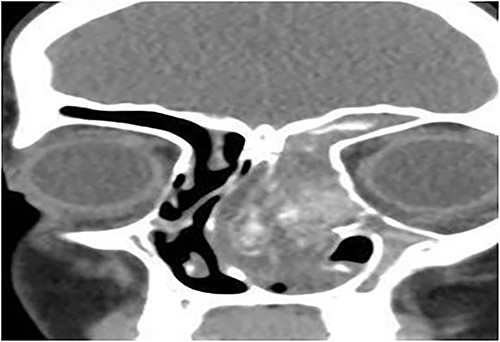

A 12-year-old female presented with unilateral left-sided nasal discharge and progressive nasal obstruction. Computed tomography (CT) scan of the paranasal sinuses (Fig. 1) confirmed the diagnosis of AFS. Functional Endoscopic Sinus Surgery (FESS) was performed to clean the sinuses from polyps, mucin and fungal debris, foll owed by medical treatment. The patient remained symptom-free for 3 years follow-up.

Coronal CT paranasal sinuses shows unilateral heterogeneous opacity of the obliterated left maxillary and ethmoid sinuses with extension through the widened remodeled ostiomeatal complex obliterating the left nasal cavity.